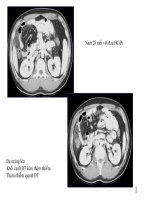

Hình nh bình th ngả ườ

Tri u ch ng h cệ ứ ọ